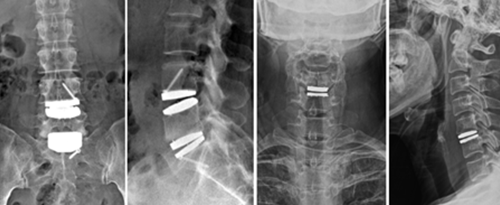

요통, 경추통, 방사통, 척추 골절, 척추 디스크, 척추관협착증, 척추전방전위증,신경차단술, 척추신경성형술, 내시경하 수핵제거술, 척추고정유합술 등

윤성훈 과장신경외과

요통, 경추통, 방사통, 척추 골절, 척추 디스크, 척추관협착증, 척추전방전위증, 신경차단술, 척추신경성형술, 디스크고주파 감압술, 양방향 / 단일공 내시경하 수핵제거술, 척추 풍선복원술, 경추/요추 퇴행성질환 교정술 등